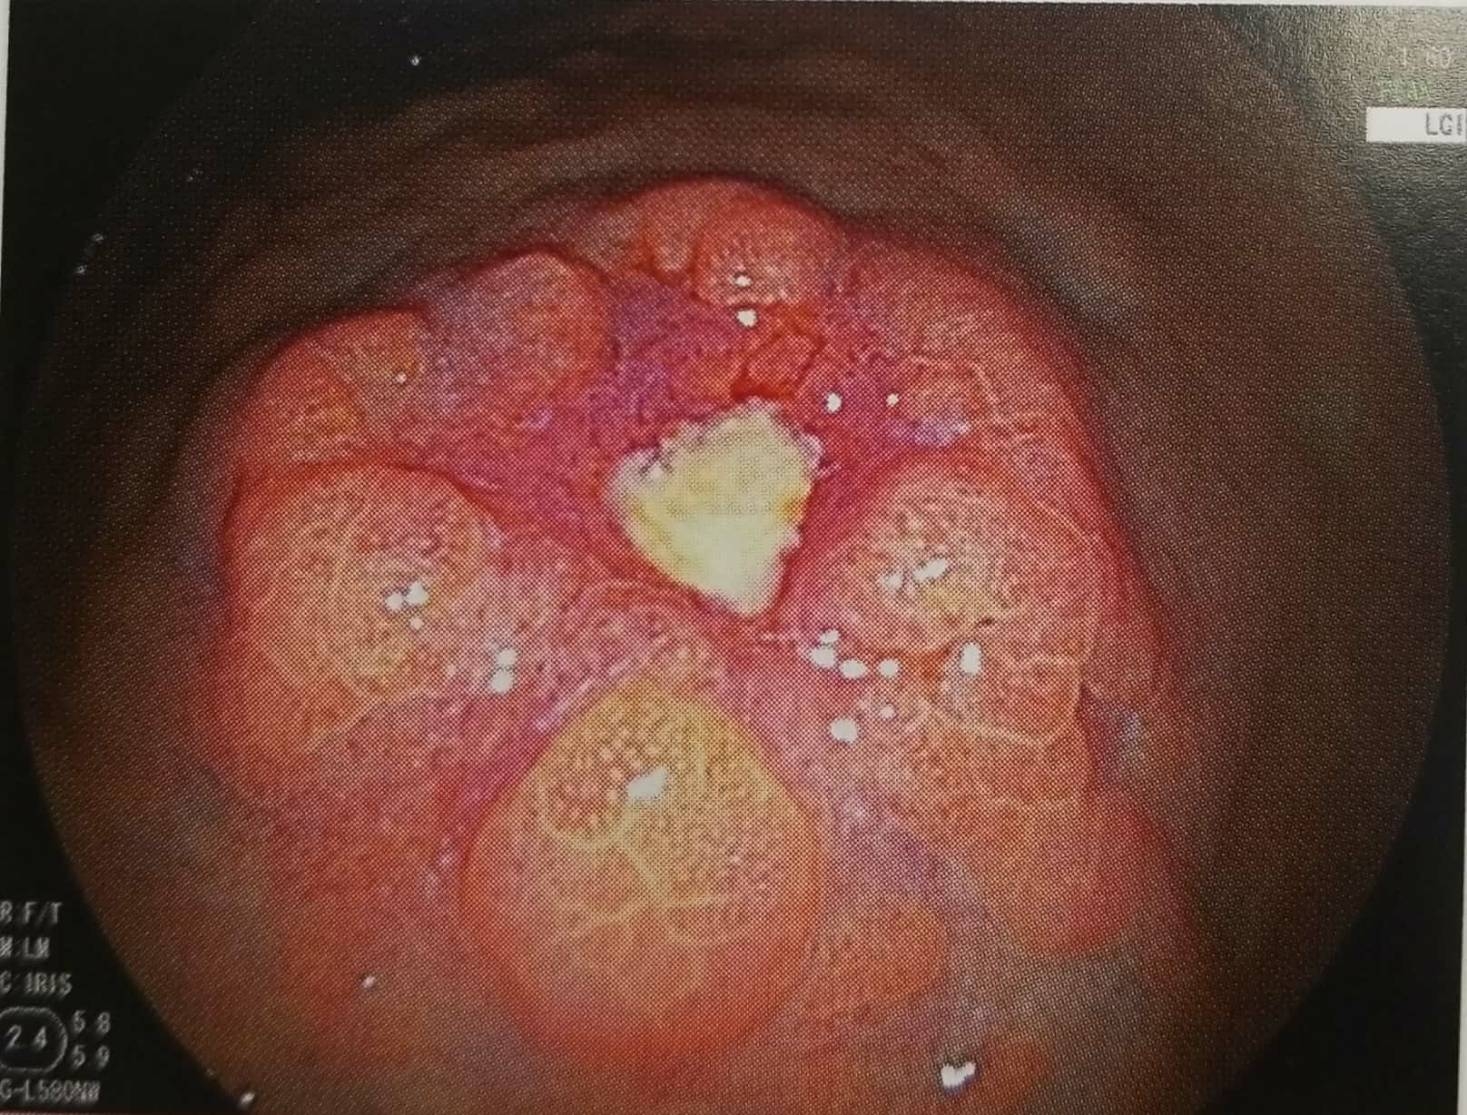

新世代内視鏡システムLASEREO(レザリオ)を導入

2種類のレーザーの発光強度比を変えることにより、状況に応じ適した観察ができ通常では見つけにくい胃癌の早期発見に役立ちます。

経鼻内視鏡の検査では、食道・胃・十二指腸などの上部消化管の様々な病気の診断ができます。胃癌と関連があるといわれるピロリ菌検査や食道や胃の組織を採取して調べる生検もできます。

もちろん胃癌の早期発見に役立ちます。ぜひ、気軽に受けていただきたい検査です。